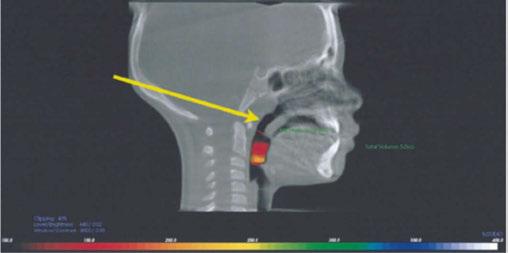

and nasal function by increasing volume.40,41 It has been shown that maxillary expansion can shrink T&A and increase the internal nasal valve (which is the first point of entry of air into the nose).42,43 Nasal valve compromise (narrowing of the internal nasal valve) has been found to result in a 7-times greater chance of TM joint capsulitis and facial and cervical myositis, via mouth breathing, when compared to other nasal obstructions (Figure 4).44

old patient who had been on CPAP for 5 years with an AHI of 118 was reduced to an AHI of 3 in 8 weeks and was able to discontinue her PAP therapy (Figure 8). Forward head posture corrections can be seen with decompression of the TM joints utilizing this technique (Figure 9). This technique is explained in Chapter 7 of Sleep Disorders in Pediatric Dentistry: Clinical Guide on Diagnosis and Management, edited by Dr. Edmund Liem, and published by Springer. Chapter 7 is authored by Dr. Edmund A. Lipskis, and titled, “Orthodontic and Dentofacial Orthopedic Treatment Strategies for Pediatric Sleep Disorders.” Advancing the entire maxilla is necessary to protract the palatine bones to increase the volume of the velopharynx (the narrowest part of the airway) (Figure 10).

Figure 10: Advancing the entire maxilla is necessary to protract the palatine bones to increase the volume of the velopharynx